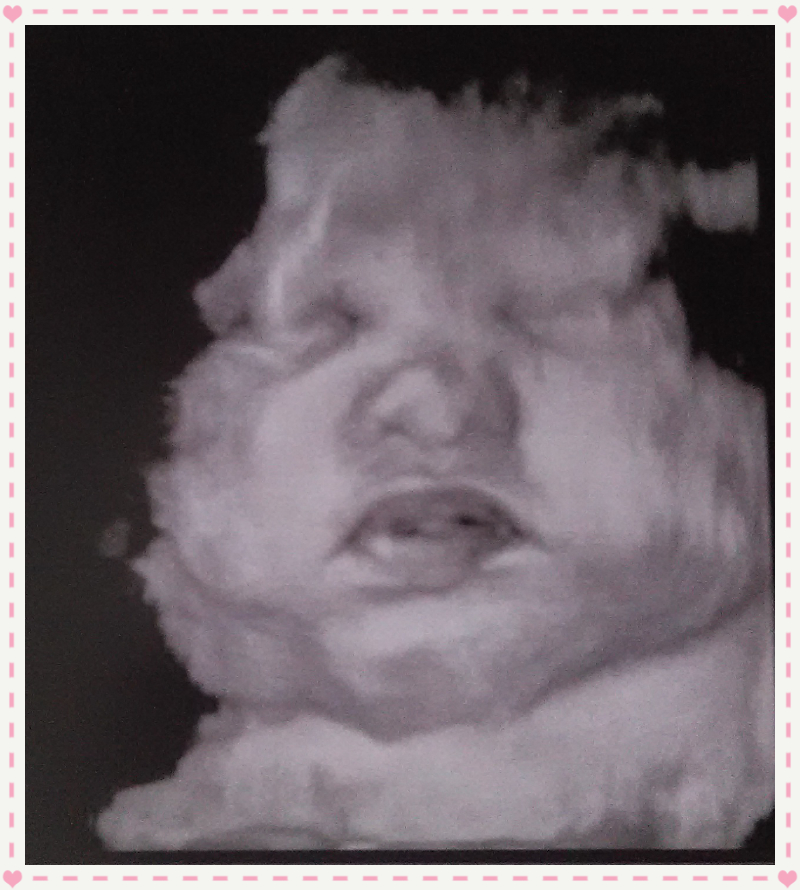

PS the pictures are from my ultrasound at 36wks (had a wonderful tech who gave us these 4d pics) just wanted to show off my chubby little monkey. DH & I just can't wait to finally meet her and have been praying non-stop that everything works out OK.